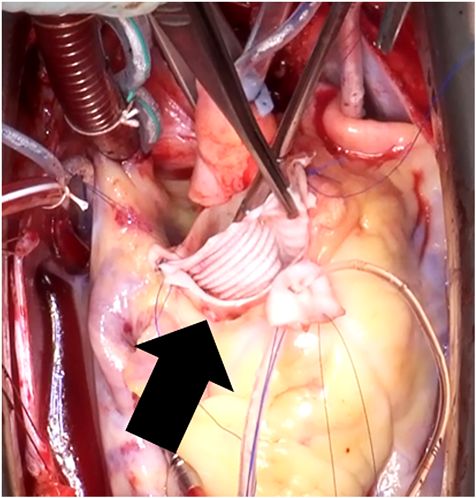

右バルサルバ洞瘤に対する手術例Surgical Repair of the Right Sinus of Valsalva Aneurysm Using an Artificial Vascular Graft Patch